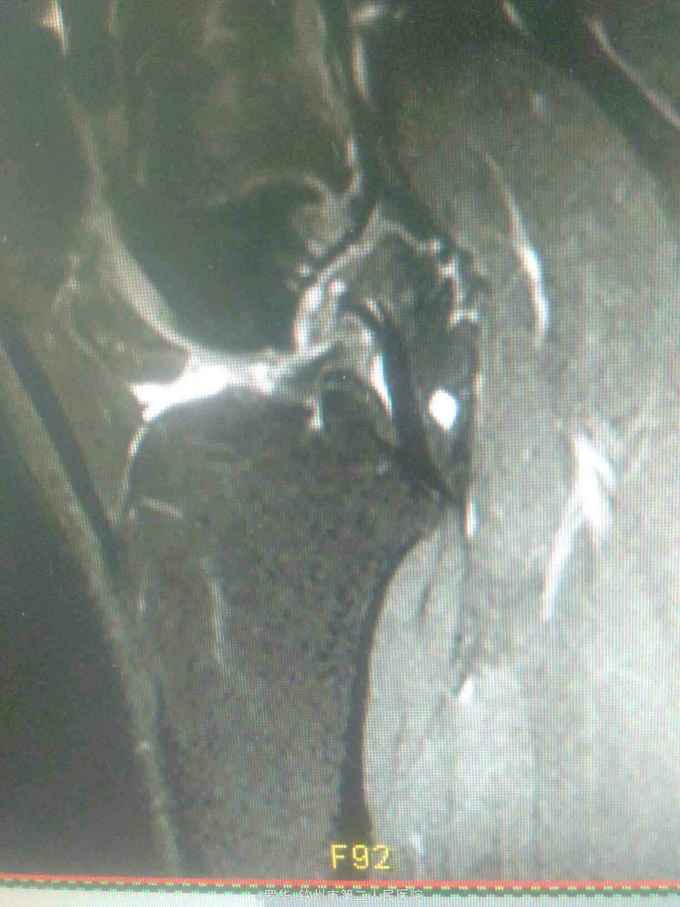

主诉:扭伤致左膝关节活动受限3月余。病史:患者男性,31岁,于入院3月余前扭伤左膝关节,致左膝关节肿痛、活动受限,尚可站立行走,但不能剧烈运动及重体力劳动,曾行磁共振检查提示左膝前交叉韧带损伤,半月板损伤,现为进上一步治疗入院。

查体:左膝关节无明显压痛,前抽屉试验阳性,侧方应力试验、麦氏征、研磨试验均阴性,膝关节屈伸活动可,余查体未见特殊。 辅查:膝关节磁共振提示左前交叉韧带损伤,左膝关节半月板损伤。

诊断:左膝关节前交叉韧带断裂,左膝关节半月板损伤。 治疗:予硬外麻下行左膝关节前交叉韧带重建术。